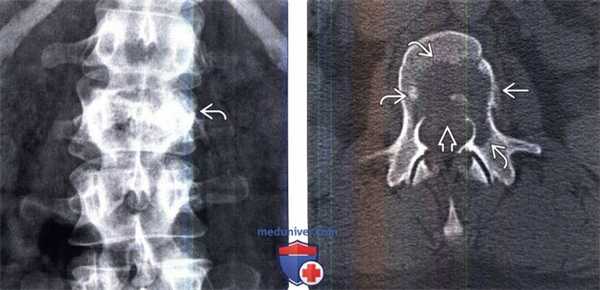

(Слева) Рентгенография в прямой проекции: опухоль Юинга L2 позвонка. Зону деструкции кости на рентгенограмме оценить сложно, однако здесь все же видно, что левый корень дуги позвонка разрушен, а тело позвонка имеет «пятнистую» структуру. Высота тела позвонка несколько снижена.

(Справа) Аксиальный КТ-срез, этот же пациент: литическое поражение тела позвонка , распространяющееся на левый корень дуги. Задняя покровная пластинка позвонка разрушена 53, а наружная истончена, здесь виден небольшой очаг периостального новообразования костной ткани.